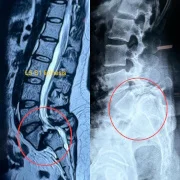

– Listhesis

Our hospital offers comprehensive lumbar spine surgery in Thane for lower back problems such as herniated discs, sciatica, lumbar canal stenosis, and degenerative spine disorders. Procedures like laminectomy, lumbar discectomy, or minimally invasive lumbar fusion help patients regain function and reduce pain. With a patient-focused approach, we ensure safe outcomes and faster rehabilitation.